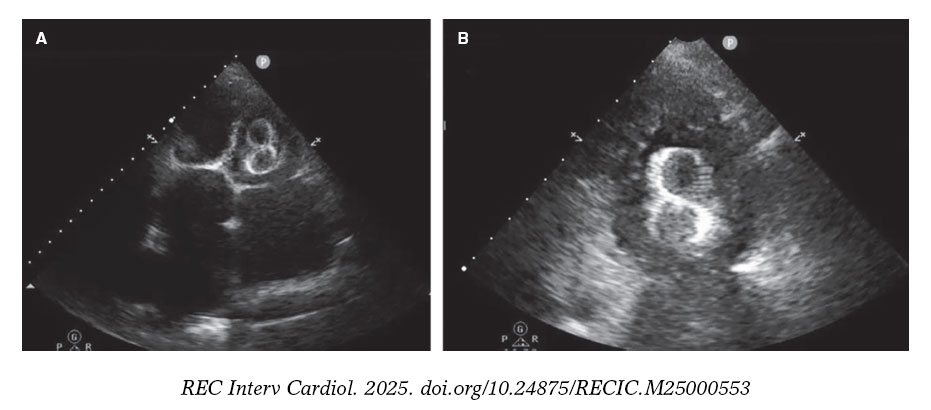

En la figura 5 y la figura 6 se muestran algunos ejemplos de embolización de dispositivos de cierre de la orejuela izquierda.

Figura 6. Ecocardiograma transtorácico (ETT) realizado 24 horas tras el implante de un dispositivo tipo LAmbre de 38 mm. A: se visualiza la migración al ventrículo izquierdo (VI), atrapado por el aparato subvalvular mitral. B: ampliación de la imagen.